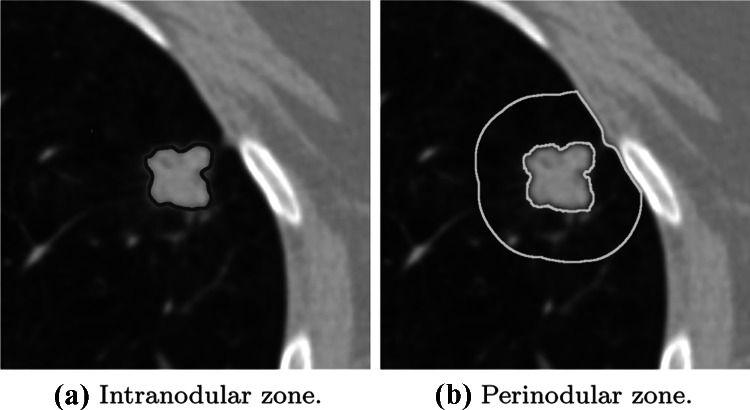

The perinodular zone segmentation algorithm was performed in four main steps (Fig. 3):

First, we retrieved the nodules coordinates presented in each examination. These positions were previously annotated by the LIDC radiologist (Fig. 3a);

For each slice of each nodule, a region of interest (ROI) was used to delimit an area surrounding the nodule. To perform this step, we chose the slice containing the largest diameter of the nodule. The ROI size as defined as a square SS window centered on the nodule, where S was 2 the nodule size (Fig. 3b);

Then, a mask was created to be used as a reference for the segmentation of the perinodular zone in the ROI. An image thresholding method eliminated the nodule, the pleura, and the vessels presented around the perinodular zone, leaving only the perinodular zone in evidence. This method based on minimizing fuzziness measures aimed to find the most appropriate threshold value to separate the anatomical parts in the images irrelevant to the characterization of the parenchyma (Fig. 3c) [23];

Finally, applying the mask (Fig. 3c) over the ROI (Fig. 3b), the final result was an image presenting only the segmented perinodular zone in each one of the nodules (Fig. 3d).

Fig. 3.

Process used for perinodular zone segmentation

A thoracic radiologist with 15+ years of experience validated the segmentation process. Due to the small differences in contrast between the final branches of the vessel trees and the parenchyma, it was not possible to remove them completely (Fig. 3). Based on the thoracic radiologist’s assessment, the segmentation algorithm was decided to be sufficiently good to be used to evaluate the parenchyma, with the exception of non-solid nodules. Therefore, the nodules labeled as non-solid by the annotations from the LIDC repository were excluded from this work.